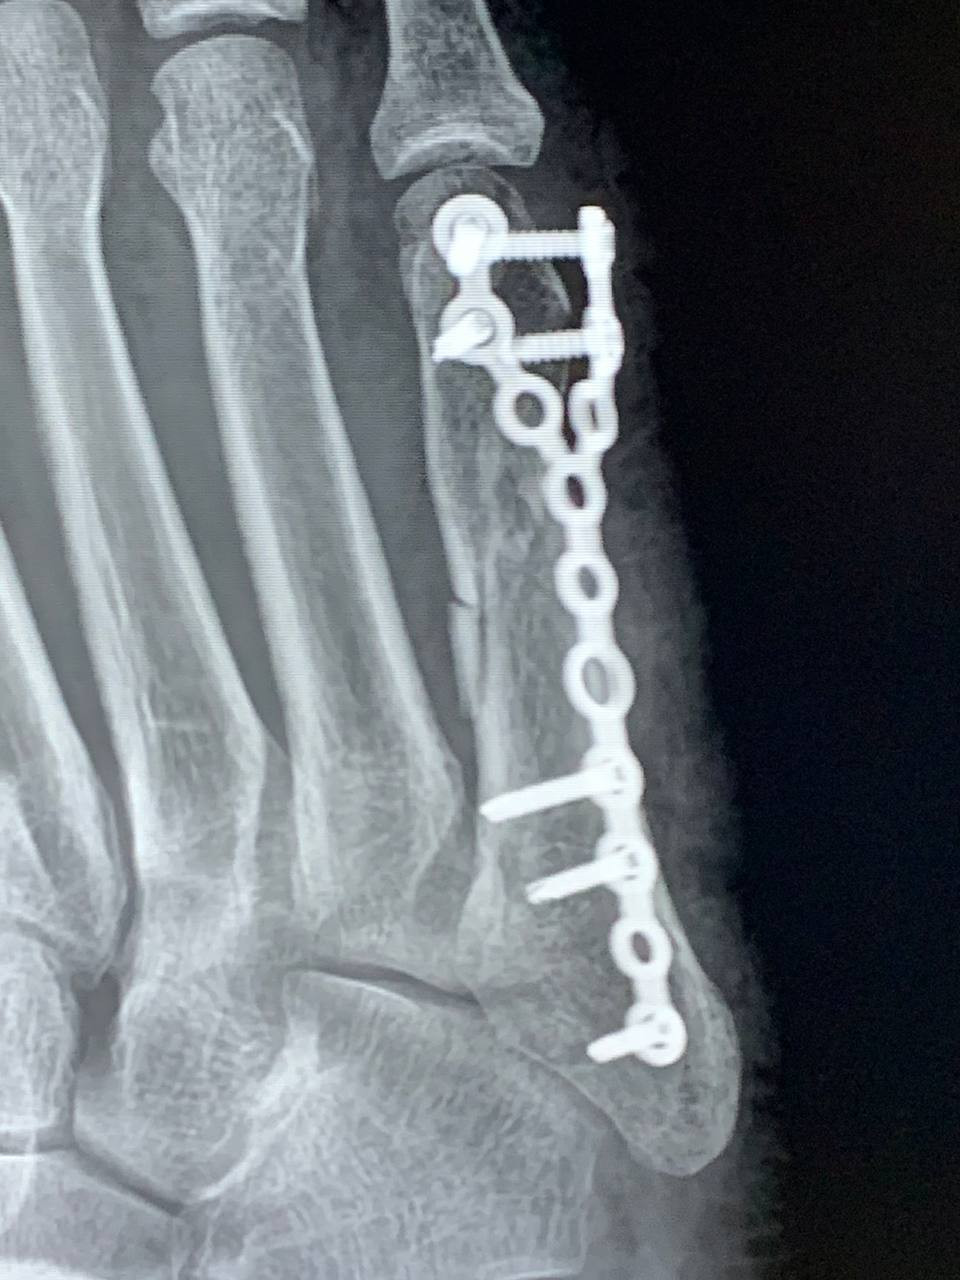

Добрый день. Мне 39 лет, получил перелом 5 плюсневой кости 3 ноября, 7 ноября прооперировали и поставили пластину. Сегодня сделал рентген 08.12.2025. Когда можно уже наступать на ногу и ходить. Срок 5 неделя наступила

Здравствуйте. По снимкам фиксация стабильная, но срок ещё небольшой. Полную опору обычно разрешают после контрольного осмотра и оценки сращения у вашего травматолога. Сейчас можно частичную нагрузку с опорой на пятку и в ортезе до решения лечащего врача.